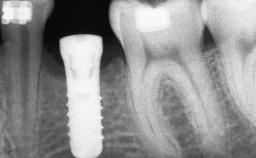

Shell Technique for Horizontal and Vertical Maxillary Bone Augmentation in a Partially Edentulous Patient with Aggressive Periodontal Disease

A 46-year-old woman was referred for treatment whose main complaints were mobility of her fixed partial dentures (right maxilla and left mandible) and periodontal bleeding during function. She also reported having taken systemic antibiotics to treat recurrent swelling in the area of the upper left molars. The patient had not seen a dentist for at least 2 years. She did not smoke and had no history of major systemic disease other than two minor orthopedic procedures some years back. The first-visit examination revealed poor plaque control, tooth mobility, periodontal disease, and a residual dentition widely associated with deep periodontal pockets.

# of Implants 3

Type of Implants One-Piece

Bone Augmentation Horizontal|Staged|Vertical